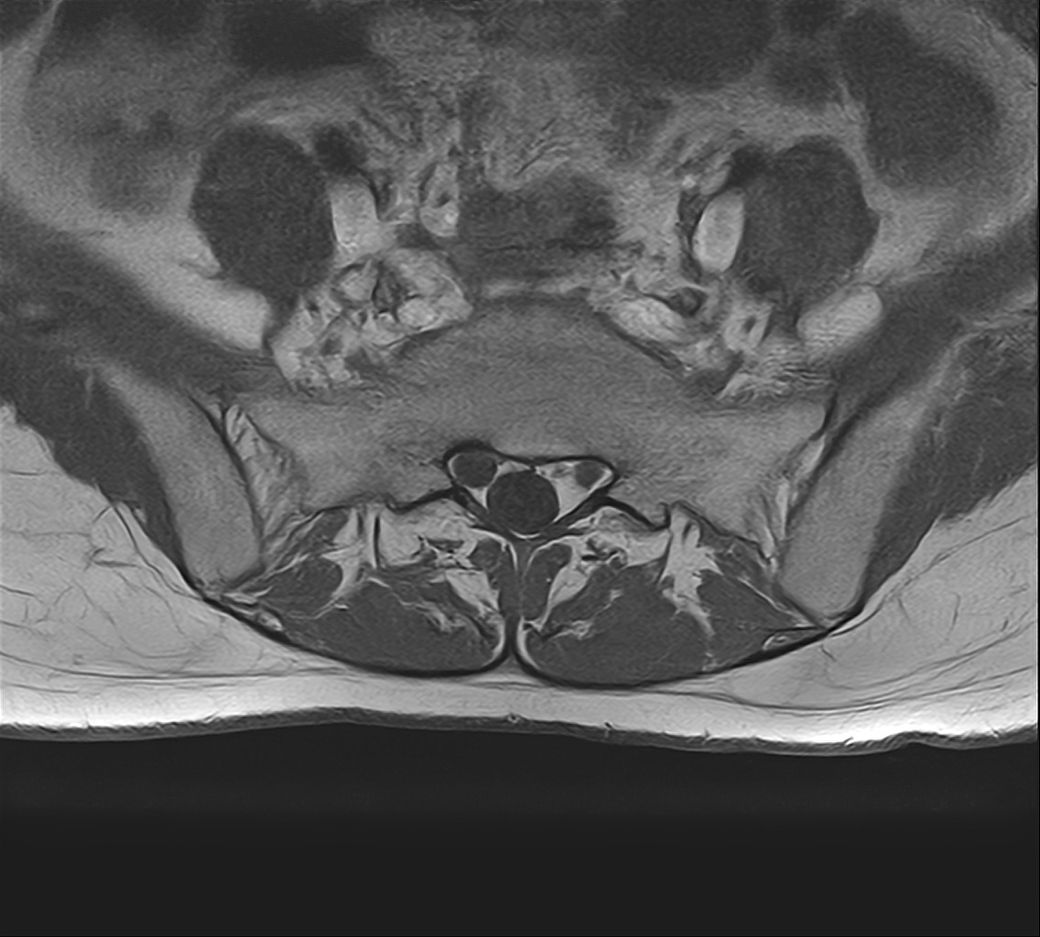

낭종s1-3번까지 꼬리뼈쪽으로 크게 나있다고했고, 단면상으로는 s2,3번이 촬영이 안되서 확인이안된다합니다. 허리디스크가 미약하게 4,5번에 있다고 했는데,

• 2번 째 사진